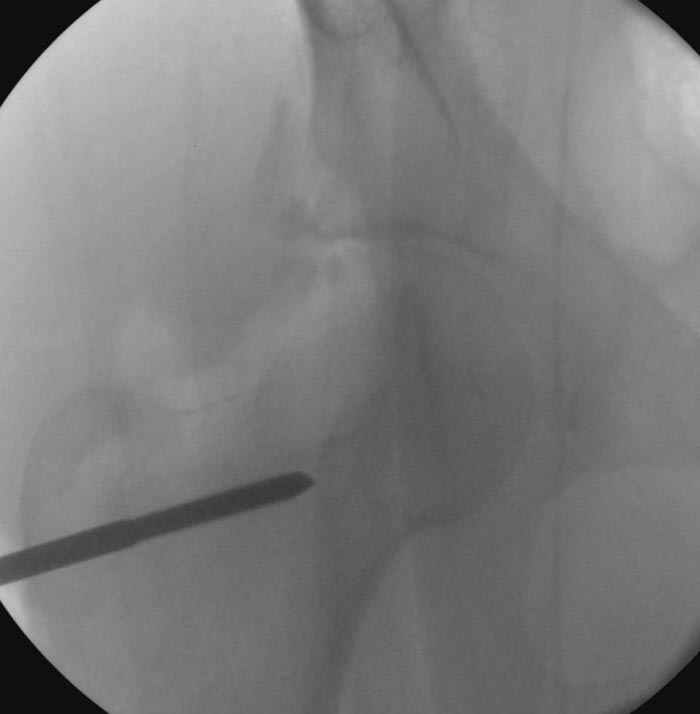

Если, например, доводится лечить больных с псевдартрозами шейки бедра, то надобность есть, и приходится. См. приложение.

На рисунке N1 предоперационный план лечения ложного сустава шейки бедра- линия ложного сустава, угол и направление введения импланта, клиновидная остеотомия в градусах и миллиметрах, второй снимок после коррекции, расчет, на сколько удлиняется конечность и размеры импланта;

N3 рисунок окончательный снимок, после операции моя рентгенограмма должен выглядеть примерно как эта картина. На N4 снимке клин перед удалением; N5 послеоперации 3 нед.; N6 окончательная рентгенограмма.